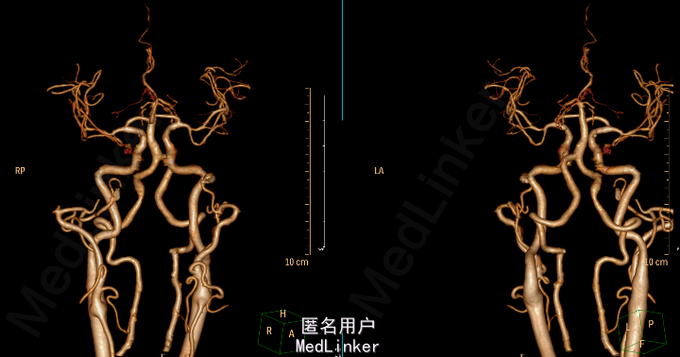

查体:T 37.0℃,P 82bpm,R 20bpm,BP 180/109mmHg。 专科情况:意识模糊,自主睁眼,无法言语,呼之不应,不配合检查。颈软;无强迫头位。眼裂对称,眼睑无下垂,眼球位置居中,各向活动五受限,未见眼球震颤,双侧瞳孔等大等圆,对光反射灵敏。双侧额纹对称,右侧鼻唇沟变浅。混合性失语,饮水呛咳。四肢肌肉萎缩,四肢肌张力增高,疼痛刺激后右上肢肌力1级,右下肢肌力2级,左侧肢体肌力2级。双侧Babinski征、Chaddock征阳性。 辅助检查:2015-06-03外院头颅MR:1.左侧额顶叶急性脑梗死;2.右侧颞枕叶、小脑、双侧基底节区及脑桥软化灶;3.脑白质缺血,脑萎缩。 2015-06-25我院头颅CTA:1.右侧小脑半球、右侧枕叶、双侧基底节区、放射冠及半卵圆中心多发缺血、梗死、软化灶;脑白质变性;脑萎缩。2.基底动脉延长、扩张,双侧椎动脉颅内段扩张(基底动脉管径最大约6mm,末端超出鞍背范围;右侧椎动脉颅内段管径最大约5mm,左侧椎动脉颅内段管径最大约4.5mm),考虑椎-基底动脉延长扩张症。3.脑动脉硬化;左侧大脑前动脉A2段闭塞;右侧颈内动脉海绵窦段、右侧大脑前动脉A2段、左侧大脑后动脉局限性狭窄;右侧颈内动脉海绵窦段钙化斑块;右侧大脑后动脉汇入右侧颈内动脉,考虑先天变异。

椎基底动脉延长扩张症(VBD) 是指椎基底动脉显著延长、扭曲并伴有管径增粗,因异常的血管搏动可致小脑功能障碍、脑梗死(BI)、脑干受压等症状。VBD 是一种少见的、病因尚未明确的全身血管广泛性病变,可同时累及微小穿支血管,其发病率较低,但各研究所报道的发病率差异较大,可能与其选择的研究人群类型不同有关。此外研究已证实,VBD危险因素有男性、高血压、吸烟、酗酒、CVD 家族史,其发病高峰主要分布在60~80岁,且更易引起缺血症状。VBD 是脑卒中的独立危险因素,对伴或未伴有VBD的脑卒中患者进行的比较研究发现高血压、VBD 形态学改变的严重程度及其影像学进展可促进VBD 患者脑梗死及脑出血的发生,BA 直径越大、水平移位越严重与脑出血越密切相关,而BA延长的程度与脑干受压、动脉瘤的类型及BA最初的最大直径呈正相关。有学者认为VBD与椎基底动脉内弹力膜的广泛缺陷及中膜网状纤维的缺乏有关。由于VBD导致血流动力学改变和对脑干及颅神经的压迫使其临床表现差异较大,其临床表现可归纳为以下4种:(1)脑神经及脑干压迫症状;(2)椎基底动脉供血不足及梗死;(3)脑出血;(4)脑积水。VBD的影像学诊断标准VBD 的影像学诊断标准, 基底动脉(BA) 或椎动脉(VA) 直径≥4.5mm,或侧方移位>10mm,且BA 全长> 29.5mm 或颅内段长度> 23.5mm。